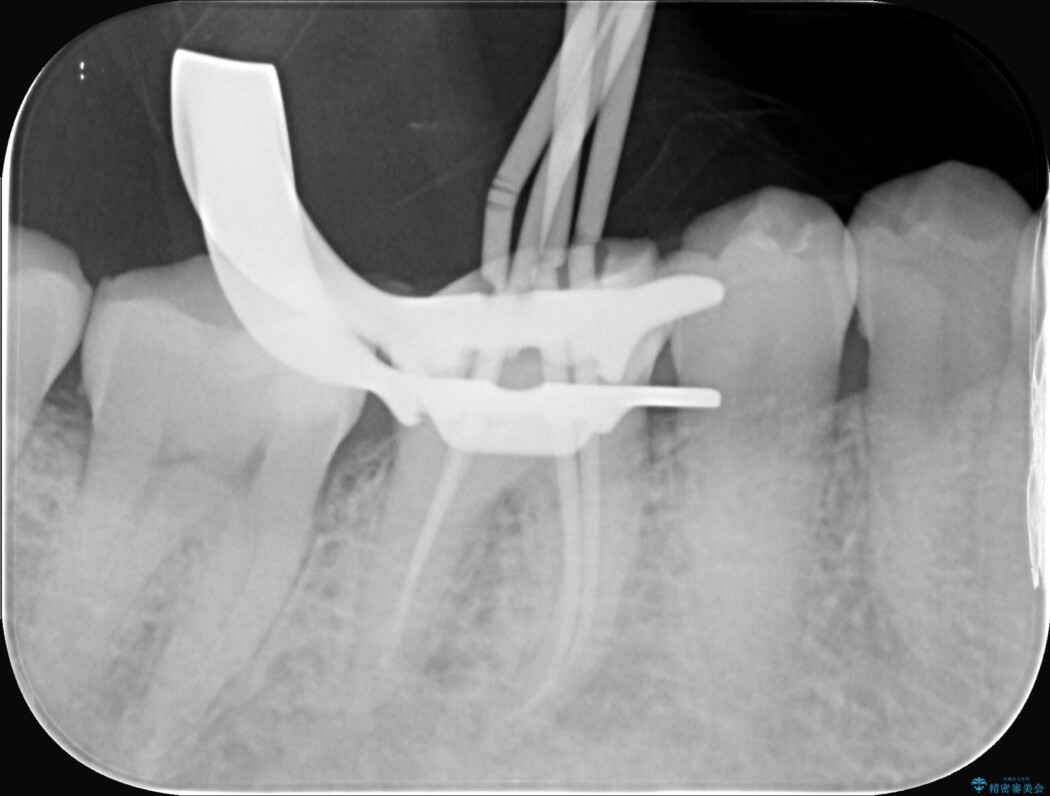

精密検査の結果、根の先に大きな病変が認められますが、根管内が狭窄し湾曲しているため、非常に難易度の高いケースです。

通常の治療器具では奥まで届かず、そのままでは再発や抜歯になるリスクが高いため、マイクロスコープを使用して根の奥まで精密に清掃・殺菌し、歯を残すための治療計画を立てました。

治療では、マイクロスコープで根の中を大きく拡大し、非常に細くなっていた神経の通り道を慎重に見つけ出しました。

次に、根のカーブに沿ってしなやかに曲がるニッケルチタンファイルを使い、根の先まで徹底的に洗浄・殺菌を行いました。汚れを完全に取り除いた後、隙間なくお薬を詰めて密閉しています。